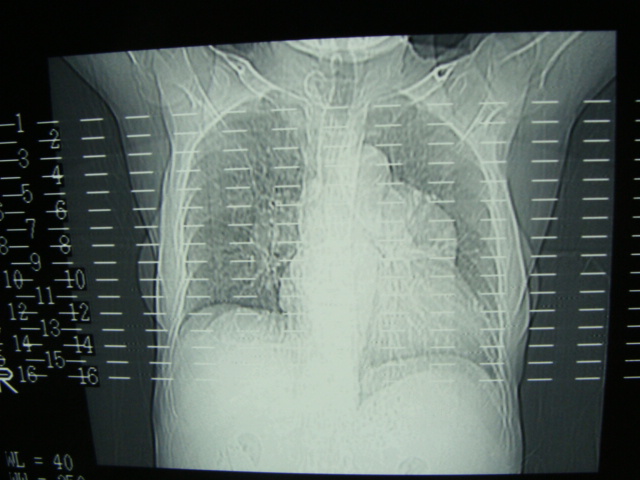

以下是引用老爱克斯新网客在2008-6-2 6:38:00的发言:[br]ct表现是肺动脉根部明显扩张,右心室增大,左房左室及右房都不大,因此可以除外风心。高血压心脏病。冠心病。定位片基本可以除外肺心病,(心肌病。心包积液更不可能)因此除外了后天性获得性心脏病。其表现也可以除外室缺。房缺。动脉导管未闭等常见的先心病。如果是原发性肺动脉高压除肺动脉根部扩张外双侧肺动脉尤其是右下肺动脉干应该也有扩张。因此我认为最大的可能是肺动脉瓣狭窄伴有窄后扩张,建议做一下彩超就知道了。期待结果。